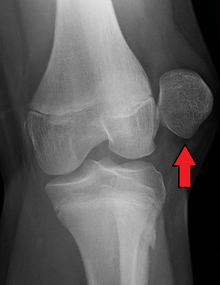

| Radiograph of a patient with patellar dislocation. Normally the patella projects over the distal femur. | |

Patellar dislocation is an injury of the knee, typically caused by a direct blow or a sudden twist of the leg.[1] It occurs when the patella (kneecap) slips out of its normal position in the patellofemoral groove, and generally causes intense pain with swelling of the knee.[1] Open or arthroscopic surgery may be used to repair damage, but are typically avoided since rates of re-injury, knee function, and patients' opinions do not differ much from conservative treatment.[2][3][4]